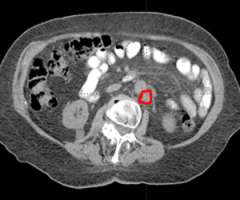

Similarly, because this specialized form of radiation involves the use of multiple radiation beam angles, expert Radiation Oncologists specialized in this technique are able to safely deliver high doses of radiation, with very sharp dose gradient outside the tumor and into the surrounding normal tissue (Figure 3).